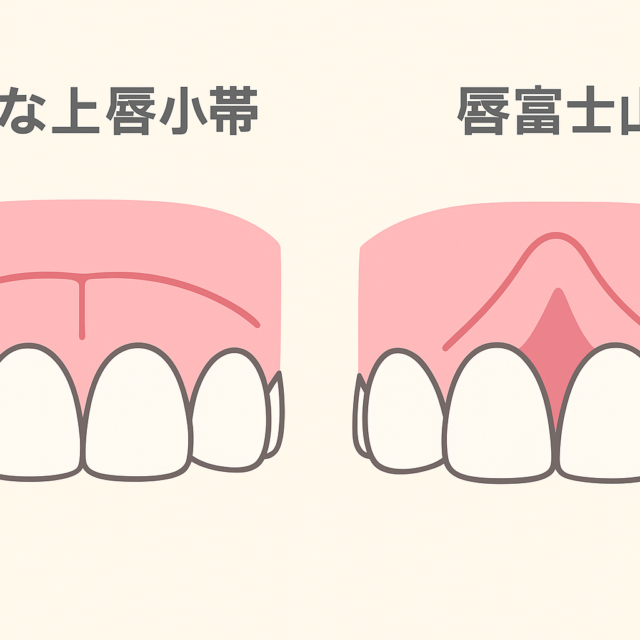

『前歯で噛みきれない。口呼吸が気になる』

※口呼吸とは、「吸う息、吐く息のどちらか一方でも口から行う呼吸法」であり、それに加えて「常時開口状態における口唇閉鎖不全(いわゆるポカン口)」も含めています。

口呼吸による弊害としては、

- 歯周病やむし歯になりやすく、口腔乾燥により口臭の原因にもなる

- 歯並びが悪くなる

- 風邪やアレルギーになりすい

- 老化を促進する

などが主に挙げられます。